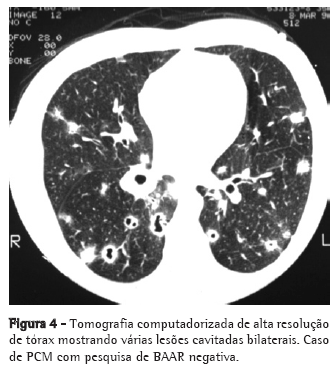

As queixas clínicas, os dados de exame físico e as alterações radiológicas apresentadas por esses doentes, na maioria das vezes, não permitiram a diferenciação segura entre as duas doenças (Figuras 2, 3 e 4).

A PCM acomete muito mais o sexo masculino (15:1), sendo a maioria dos pacientes formada por lavradores ou ex-lavradores com idade entre 30 e 50 anos. Comumente são oligossintomáticos, com poucos achados de exame físico, podendo, no entanto, apresentar exuberantes alterações radiológicas torácicas tanto na radiografia simples quanto na tomografia computadorizada de alta resolução.(11-15)

O acometimento pulmonar é geralmente bilateral, com predomínio nos campos médios e regiões medulares.(16,17)

Por sua vez, a TB acomete ambos os sexos em qualquer idade, com a maioria dos pacientes se apresentando sintomáticos, com exame físico comprometido e alterações radiológicas, em geral, de predomínio em segmentos superiores e posteriores, podendo também ser bilaterais.